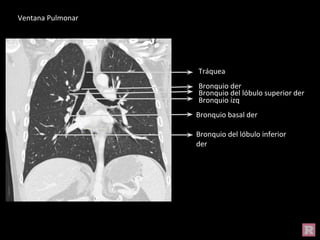

Bronquio del lóbulo inferior

der

Tráquea

Bronquio izq

Bronquio basal der

Bronquio der

Bronquio del lóbulo superior der

Ventana Pulmonar